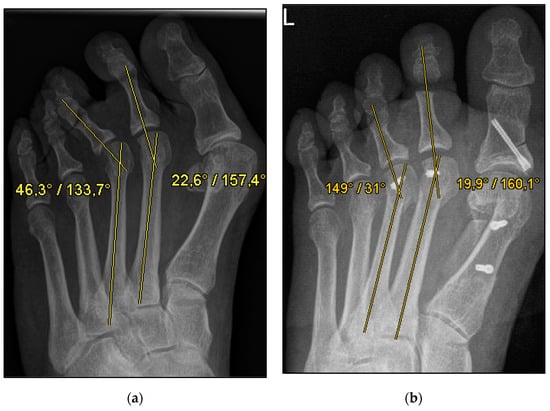

Figure 2.

Pre- and postoperative radiographic results of combined hallux valgus surgery and Weil osteotomy of metatarsal 2 (group B without screw), right foot. (a) Weight-bearing radiograph: anteroposterior view preoperative, (b) weight-bearing radiograph: anteroposterior view, 2 months postoperative.

We collected the following data from the weight-bearing dorsoplantar foot radiographs after a mean follow-up period of 16 weeks (3.6 months). With no significant difference between groups, the mean MTP angle changed from 9.24° to 12.99° preoperative to postoperative (medial deviation: −n, lateral deviation: +n). As can be seen from the mean SEM in Table 2 and Figure 4 and Figure 5, the maximum medial and lateral deviations from pre- to postoperative were significantly different. The mean MTP only changed from 9.3 to 12.9 and was in the range of a mild lateral deviation. This was also observed equally in both groups (p > 0.05). Of note, the postoperative visibility of the joint space was documented significantly more often in the group without screw fixation; this means the space between the subchondral bone of the metatarsal and the toe was seen without overlay (p < 0.05).

The underlying assumption of our study and the knowledge gained from our results can be further elaborated upon. An inharmonious transverse plane alignment can also be corrected with Weil osteotomy and does not require osteosynthetic fixation of the displaced metatarsal head [24]. The results confirm, based on postoperative weight-bearing radiographs, that the surgically induced correction is maintained regardless of screw fixation. An objectifiable criterion was the metatarsophalangeal angle measured pre- and postoperatively using weight-bearing radiographs in the dorsoplantar view (Figure 1 and Figure 2). In both treatment groups, it was possible to bring the maximum axis deviation closer to the mean value; the mean difference between pre- and postoperative metatarsophalangeal angle was only 3.8°. On average, 10.6 degrees were required to achieve the desired surgical result, regardless of screw fixation (Figure 4 and Figure 5). However, the significantly higher possibility of viewing the affected metatarsal joint space postoperatively can also be considered a successful outcome of the restoration without screw fixation. The visibility of the articular surface, in turn, proves the centering of the metatarsal head in the transverse plane as well as a sufficient correction in the sagittal plane (Figure 6 and Figure 7) [25]. Again, the inability to view the joint space indicates that inadequate correction of the claw toe deformity as well as the metatarsal, which was considered “too long”, was performed [1,14,26].